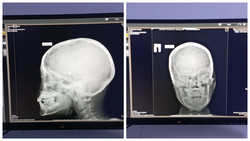

Жалал-Абадда бир туугандардын оюнунан кийин 9 жаштагы баланын көзү агып калды. Ок мээсине кирип кеткен